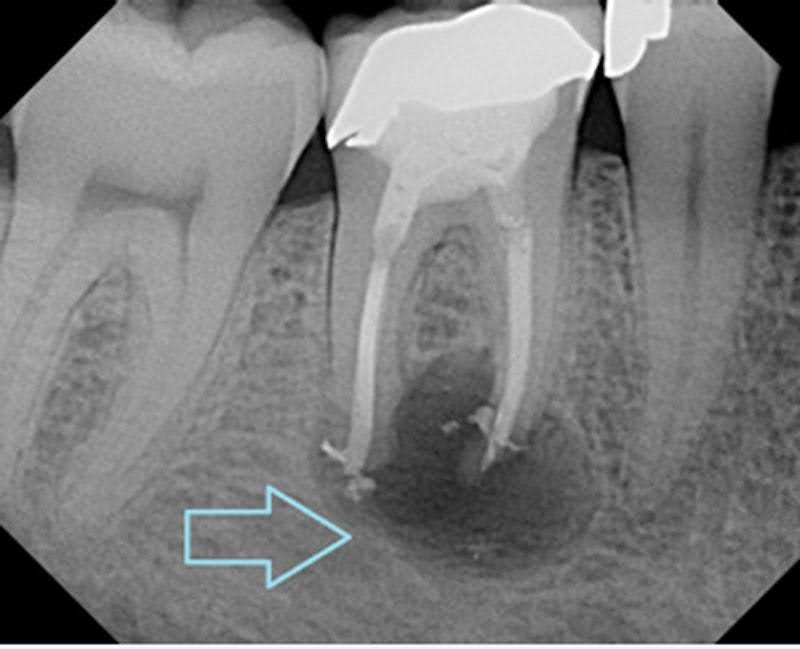

5. Tooth Abscess (Infection)

An abscess is a serious dental infection that develops at the root of a tooth or between the gum and tooth. This condition can cause intense pain, especially when chewing.

An abscess is a serious infection at the root of the tooth.

Treatment:

- Root canal

- Antibiotics

- Extraction (if necessary)

- X-rays